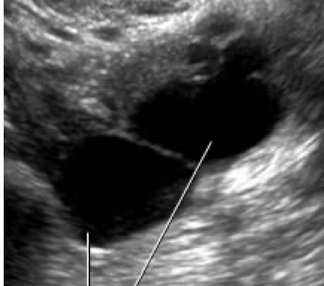

What is this

Ovarian Cancer